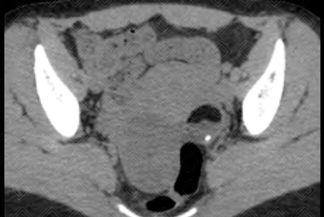

Texto alternativo para a imagem Figuras 1, 2 e 3. Créditos: Dra. Elazir Mota - Rio de Janeiro/RJ.

Descrição das figuras 1, 2 e 3: Tomografia computadorizada do abdome. Estudo pré e pós-contraste (fase portal). Observa-se lesão heterogênea, bem definida, com nível líquido-gorduroso e foco de calcificação ("sinal da pokebola"). A gordura é identificada por uma densidade abaixo negativa (seta vermelha). Essas características de imagem permitem que o diagnóstico de teratoma ovariano maduro possa ser sugerido.

• Tomografia computadorizada do abdome e pelve: O estudo será realizado com contraste venoso idealmente, para melhor caracterização da lesão. A TC, no caso específico do teratoma maduro, possui uma sensibilidade alta para sua caracterização (cerca de 98%). Nela encontram-se áreas com densidade negativa (conteúdo gorduroso), calcificações e, na maioria dos casos, o nódulo mural (Rokitansky) no interior da formação cística. Nesses casos, é possível sugerir o diagnóstico (como nas imagens acima);